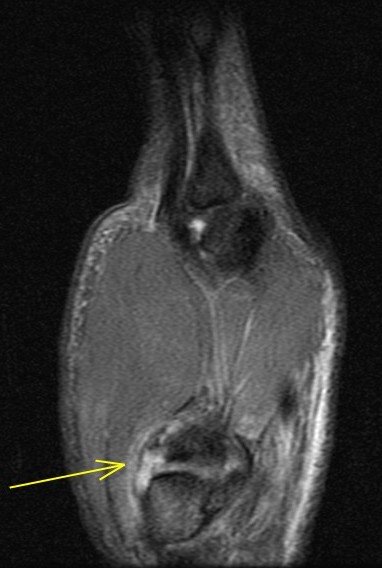

26 y/o crashed on a skateboard.

Patient has torn the deep anterior oblique ligament (beak), and sprained the superficial anterior oblique ligament, posterior oblique ligament and first intermetacarpal ligament. Also a sprain of the dorsoradial ligament. The joint has reduced but the patient related that he can slip it in and out easily. First images are from a dedicated thumb exam and the last image is from the wrist exam.

trapeziometacarpal dislocation